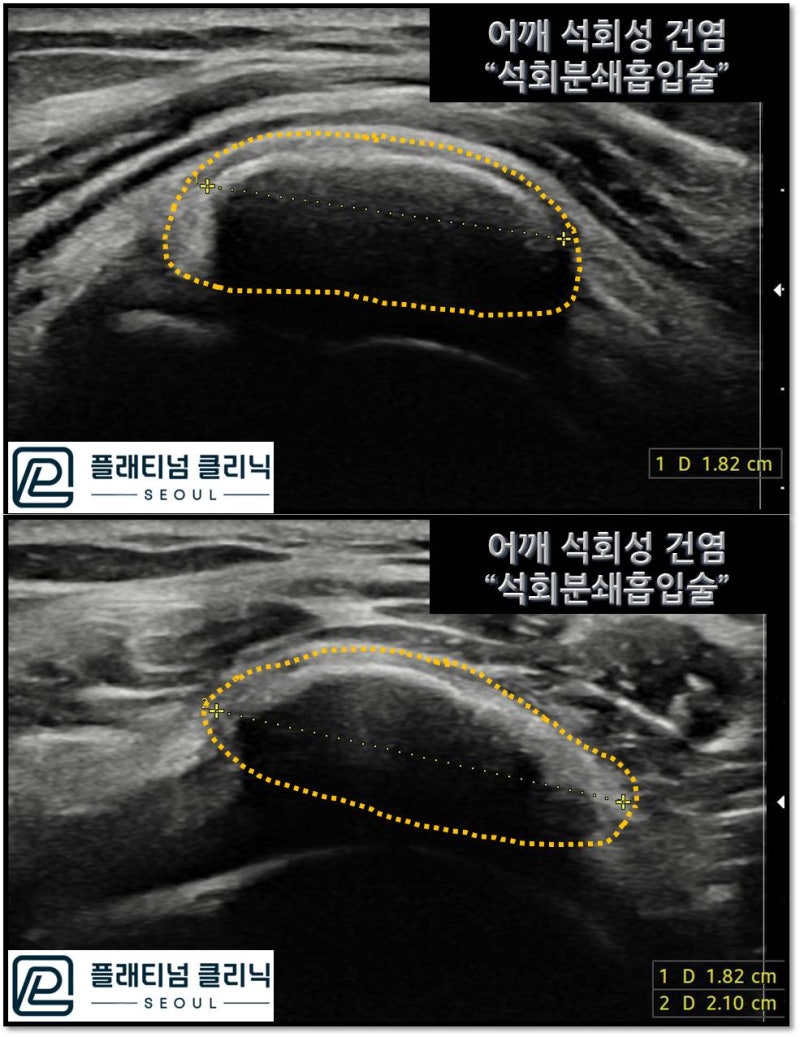

X-ray를 보면 빨간 원 안에 노란점선으로 표시된 부위가 하얗게 보이는데 이것이 석회입니다. 엄청 큰 석회가 있는 것이 확인됩니다. 초음파를 통해 석회의 정확한 크기와 양상, 위치를 확인하였습니다.

초음파상 약 2.10*1.82cm 크기의 거대한 석회가 관찰되며 위치는 극상근의 전체를 거의 덮고 있을 정도로 큰 석회로 관찰됩니다. 석회의 양상은 단단한 석회와 찐득한 석회가 공존해 있는 것으로 판단됩니다. 석회분쇄흡입술을 통해 석회를 제거하였습니다. 시술 후 주사기 사진을 보여드리겠습니다.